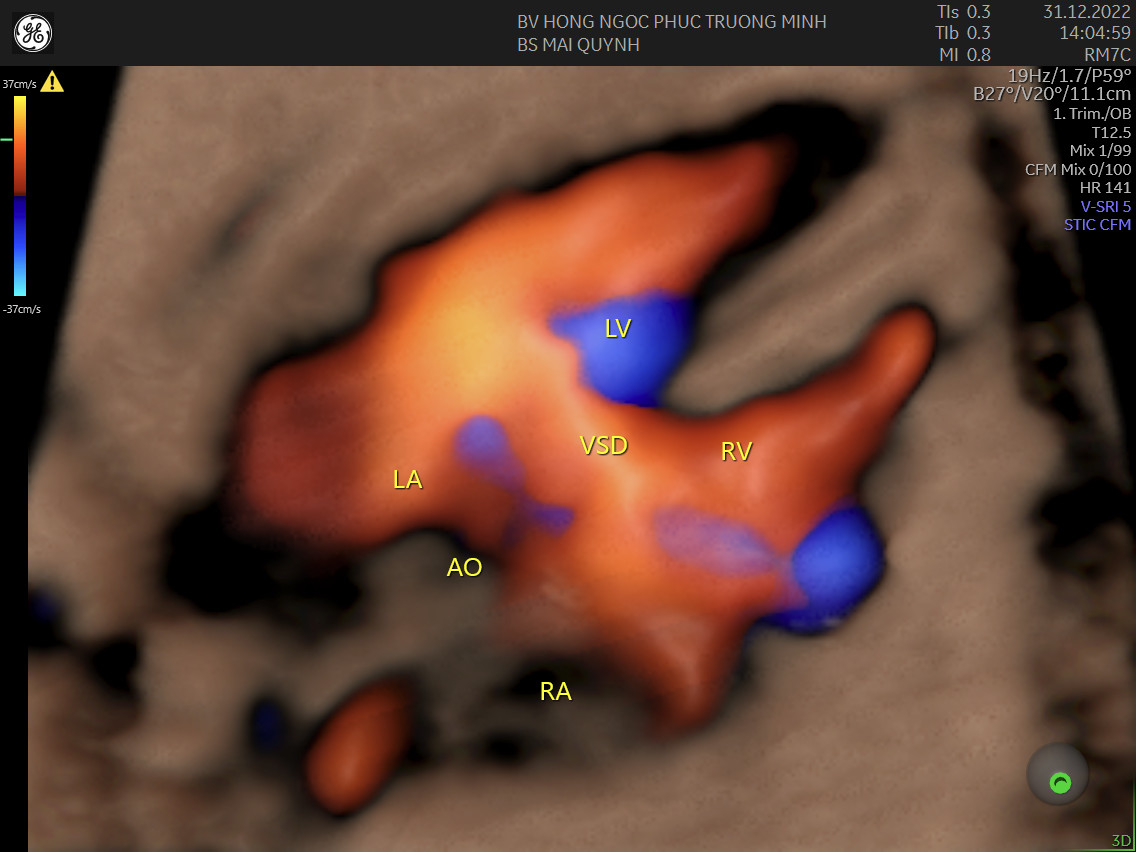

Hình ảnh thông liên thất ở thai 30 tuần với kĩ thuật 4D STIC tim thai.Siêu âm tim thai là một kỹ thuật chuyên sâu, ngoài kiến thức, kinh nghiệm và trình độ chuyên môn của các bác sĩ, trang thiết bị cũng là một phần rất quan trọng. Hiện nay, khoa Sản Phụ khoa - Bệnh viện Đa khoa Hồng Ngọc Phúc Trường Minh là cơ sở đầu tiên và duy nhất trên cả nước sở hữu máy siêu âm hiện đại nhất thế giới - Voluson Expert 22 của hãng GE Healthcare. Với công nghệ UltraHD, Augment, Shadow Reduction.... cùng các kĩ thuật tái tạo tim 3D, 4D STIC cho phép tăng độ chính xác trong chẩn đoán bất thường tim thai cũng như minh họa cho cha mẹ hình ảnh thai nhi một cách sinh động và trực quan nhất có thể.